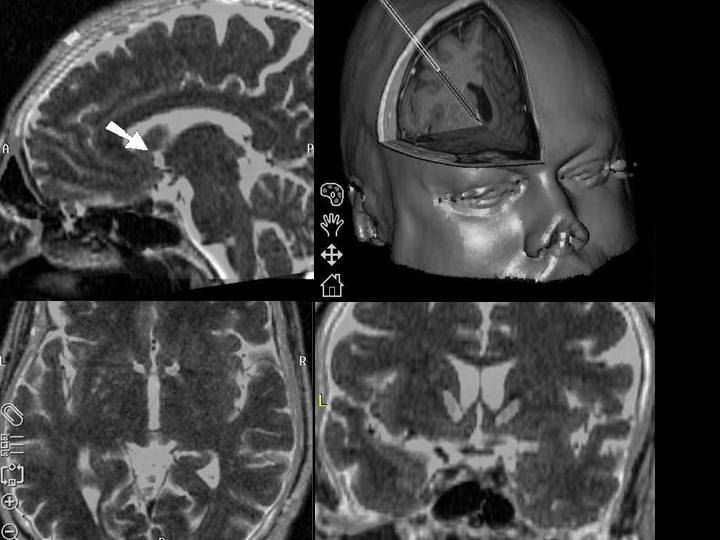

accumbens

ocd